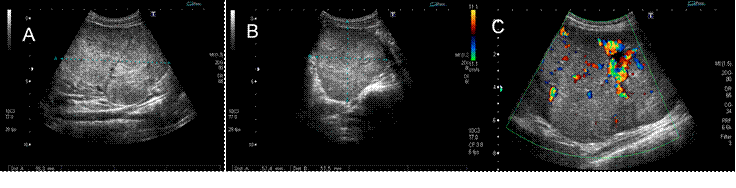

Se solicitó al servicio de Radiología Intervencionista la realización de biopsia renal (Imagen 2), cuyo reporte histopatológico fue oncocitoma híbrido renal izquierdo.

Ultrasonido modo B: A, Vista longitudinal. B, vista transversal. C. Ultrasonido Doppler. Masa hiperecoica, bien delimitada, lobulada, heterogénea por ecos de mayor intensidad en su interior que a la aplicación del Doppler color muestra alta vascularidad.

Imagen 2 Biopsia renal guiada por ecografía